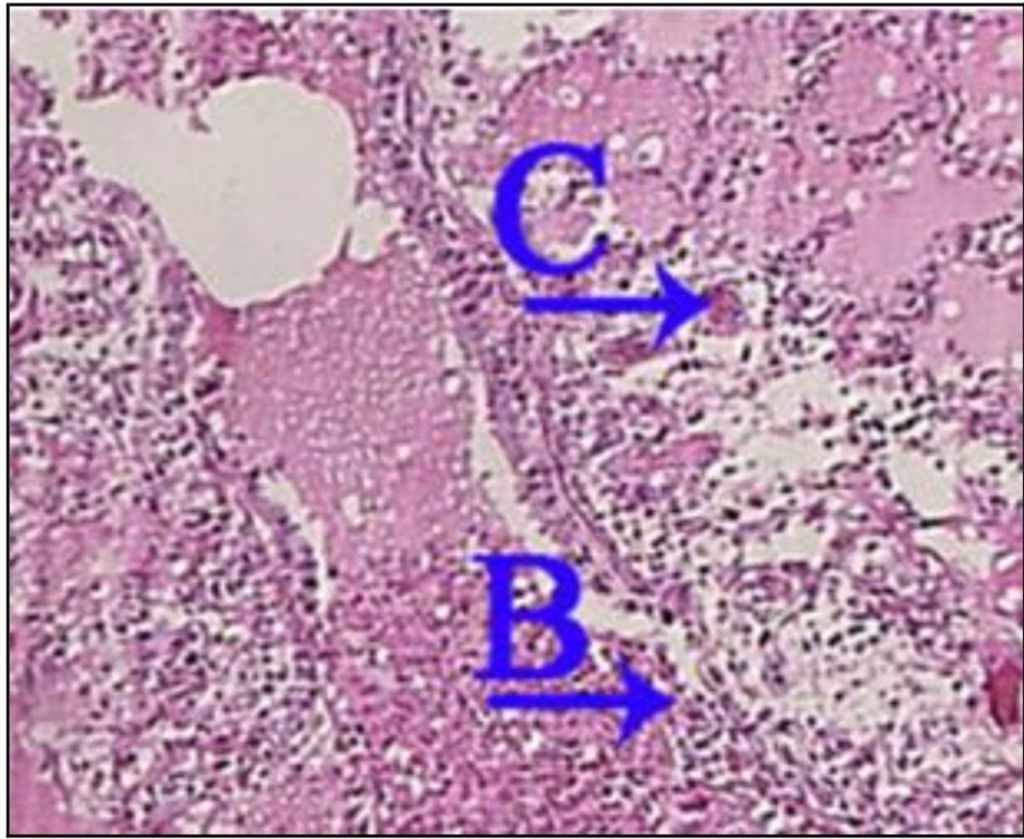

Question 72

Question

What is the correct answer at point A?

Answer

• - lésion segmentaire hétérogène

• - lésion de la muqueuse bronchique

• - lésion alvéolites suppurée

• - épithélium respiratoire

• - lumière comblée de nécrose suppurée

Question 73

What is the correct answer at point B?

Question 74

What is the correct answer at point C?

Question 75

What is the correct answer at point D?

• -lésion de la muqueuse bronchique

Question 76

What is the correct answer at point E?